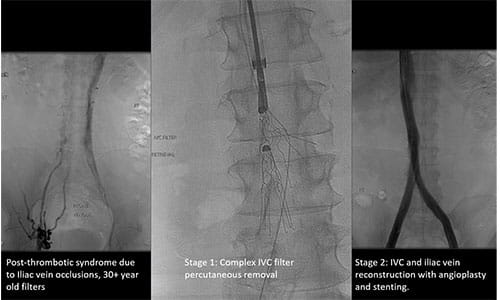

Another condition treated within the CCVC is DVT. Approximately half of patients with DVT develop post-thrombotic syndrome (PTS), experiencing symptom burden that includes leg pain, swelling, heaviness and — in very advanced cases — ulceration.

UH Cleveland Medical Center, with Dr. Harth as the local Principal Investigator, is participating in the C-TRACT Trial, a randomized study funded through the National Institutes of Health's National Heart, Lung, and Blood Institute (NHLBI) that seeks to determine whether catheter-assisted EVT is effective in reducing the severity of PTS in eligible patients.

“There are a number of studies that suggest there is a benefit to recanalization of the iliac vein via stent placement as compared to standard medications, compression therapy and wound care, but there is no definitive data,” Dr. Harth says. “We are excited to be the only site in our region recruiting patients for this pivotal study of PTS best-practices care.”